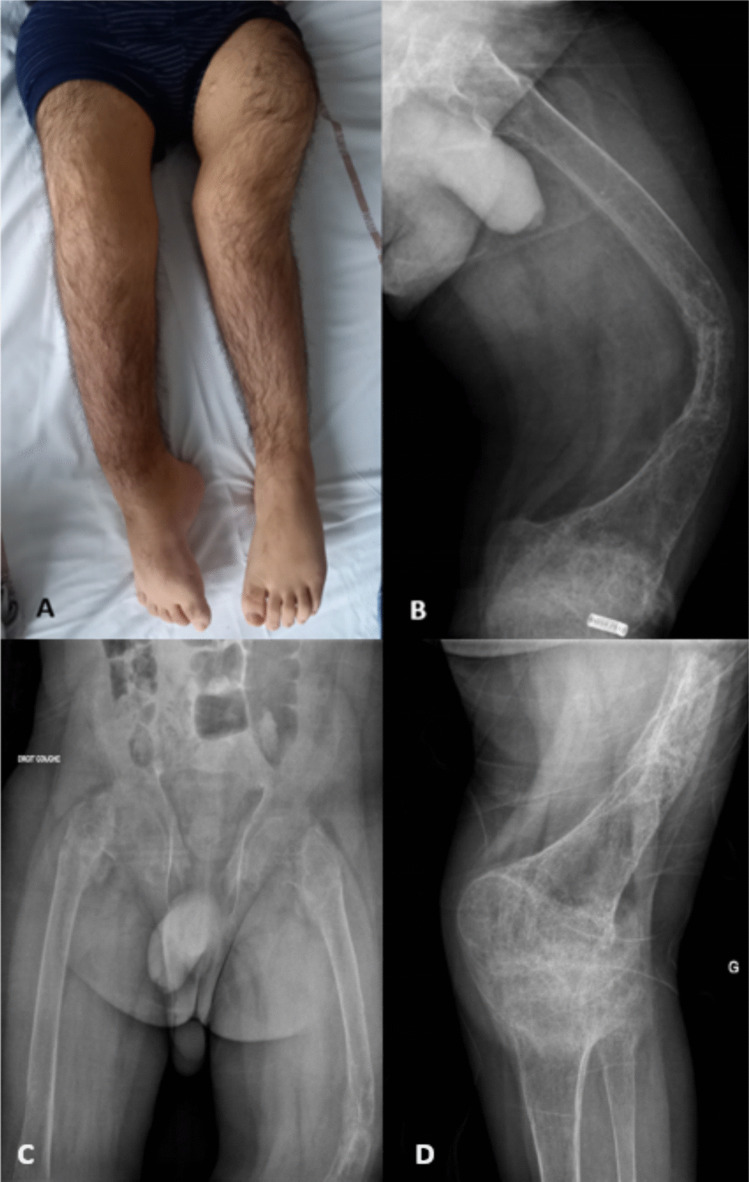

肿瘤诱导骨软化症(TIO)是一种罕见的副肿瘤综合征,由过量的成纤维细胞生长因子23 (FGF23)引起,导致低磷血症和骨软化症。它通常表现在成年期,小儿病例极为罕见。早期诊断对于预防不可逆的骨骼畸形至关重要。我们报告的情况下,一个19岁的男子严重下肢畸形和丧失行动,因为童年。最初误诊为x连锁低磷血症(XLH),并使用burrosumab治疗,基因检测排除了遗传性低磷血症。进一步检查显示右侧股骨有分泌fgf23的间充质肿瘤,证实了TIO。手术切除肿瘤导致生化缓解,而布罗单抗治疗有助于疼痛缓解、功能改善和骨矿物质密度增加。组织学检查提示潜在的肿瘤修饰与布罗单抗暴露有关。本病例强调了儿科发病TIO的诊断挑战,强调了在早期低磷性骨软化伴严重畸形的病例中考虑致癌佝偻病的重要性。尽管治疗,持续性骨骼异常的风险强调了早期识别和干预的必要性。此外,布鲁苏单抗在治疗低磷血症和症状方面显示出临床疗效,这表明在手术延迟或无法手术时,它在TIO中具有治疗作用。儿科发病的TIO是一个未被充分认识的实体,如果不及早诊断,可能导致严重的残疾。这个病例强调了早期肿瘤识别的重要性。

Tumor-induced osteomalacia (TIO) is a rare paraneoplastic syndrome caused by excess fibroblast growth factor 23 (FGF23), leading to hypophosphatemia and osteomalacia. It typically manifests in adulthood, with pediatric cases being exceedingly rare. Early diagnosis is critical to prevent irreversible skeletal deformities. We report the case of a 19-year-old man with severe lower limb deformities and loss of ambulation since childhood. Initially misdiagnosed with X-linked hypophosphatemia (XLH) and treated with burosumab, genetic testing ruled out hereditary hypophosphatemic disorders. Further evaluation revealed an FGF23-secreting mesenchymal tumor in the right femur, confirming TIO. Surgical resection of the tumor led to biochemical remission, while burosumab treatment contributed to pain relief, functional improvement, and increased bone mineral density. Histological examination suggested potential tumor modifications linked to burosumab exposure. This case highlights the diagnostic challenge of pediatric-onset TIO, emphasizing the importance of considering oncogenic rickets in cases of early hypophosphatemic osteomalacia with severe deformities. The risk of persistent skeletal abnormalities despite treatment underscores the need for early recognition and intervention. Moreover, burosumab showed clinical efficacy in managing hypophosphatemia and symptoms, suggesting a therapeutic role in TIO when surgery is delayed or inoperable. Pediatric-onset TIO is an underrecognized entity that can lead to severe disability if not diagnosed early. This case underscores the importance of early tumor identification.